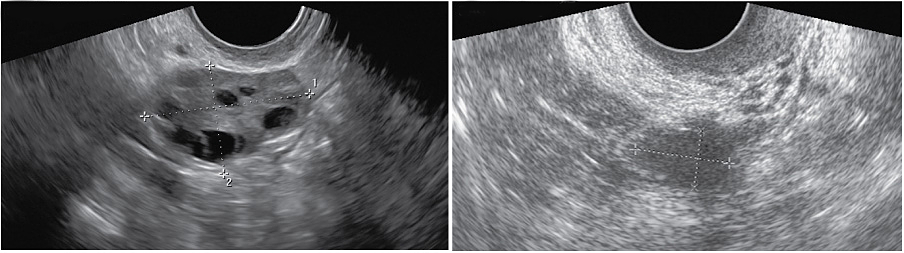

Созревание фолликула в яичнике: этапы и процессы